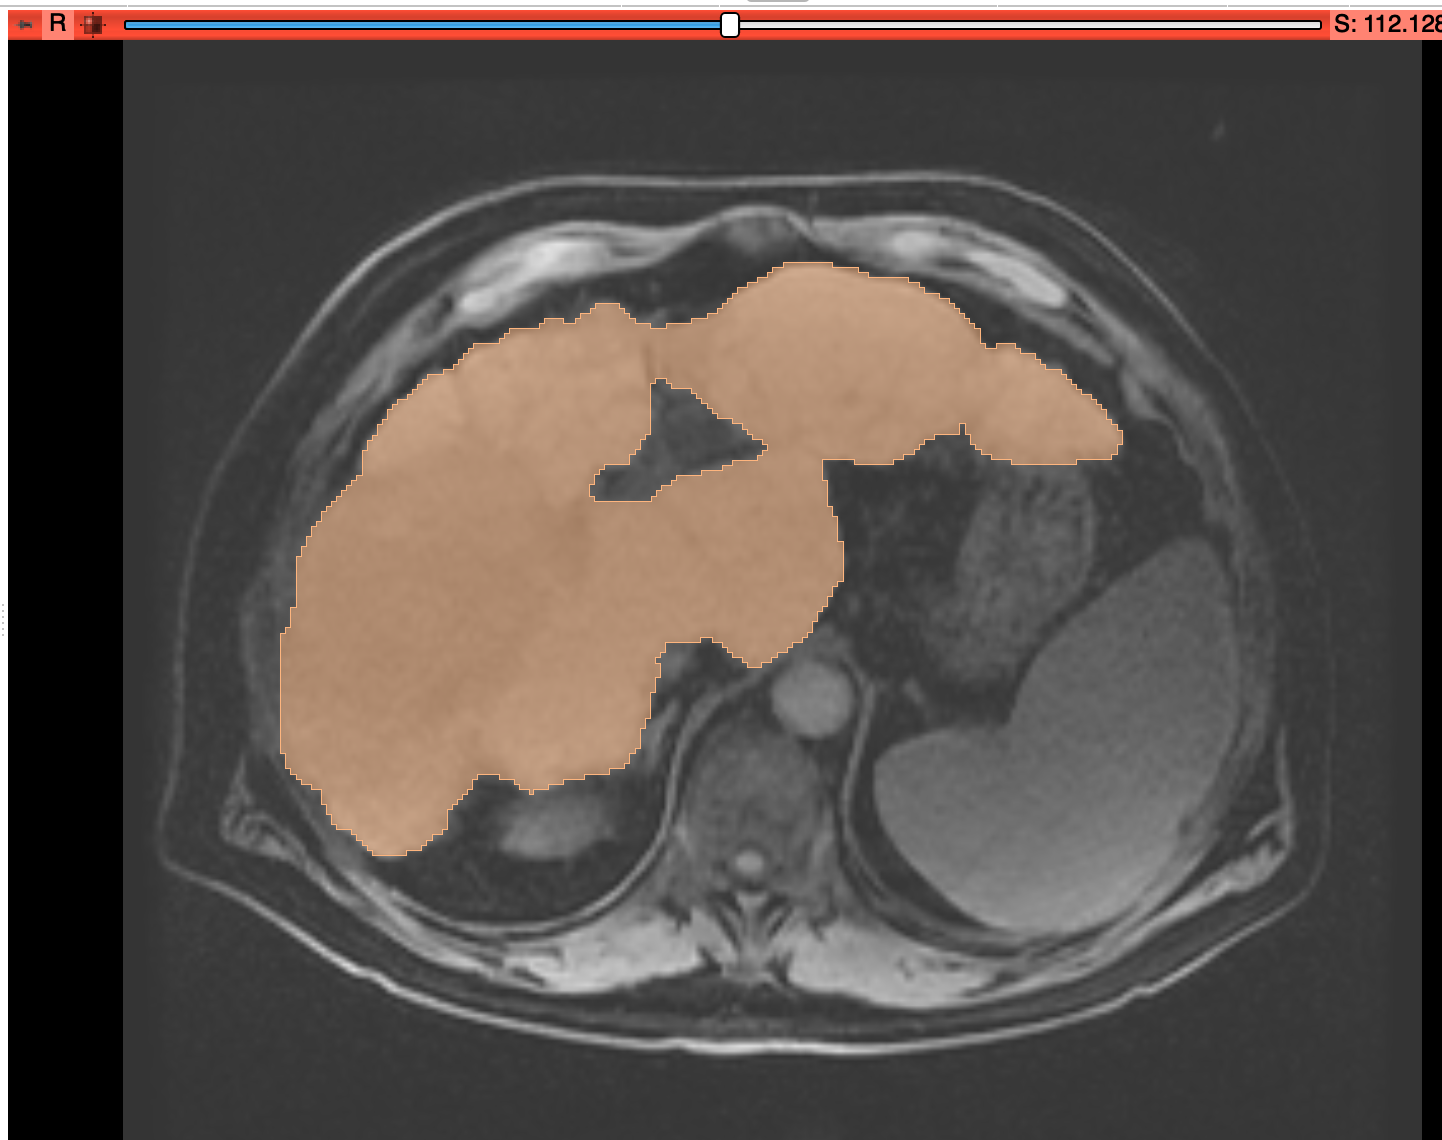

MeVisLab-exported segmentation overlaid in Slicer